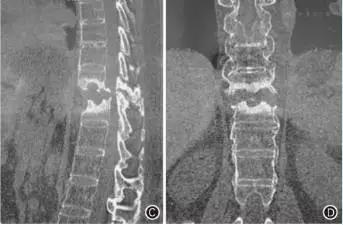

强直性脊柱炎症状主要表现为:臀髋部或腰背部疼痛和/或发僵,尤以卧久(夜间)或坐久时明显,翻身困难,晨起或久坐起立时腰部发僵明显,但活动后减轻。有的患者感臀髋部剧痛,偶尔向周边放射。疾病早期疼痛多在一侧呈间断性,数月后疼痛多在双侧呈持续性。随病情进展病变由骶髂关节向腰椎、胸颈椎发展,则出现相应部位疼痛、活动受限或脊柱畸形,要及早治疗,你可以去试试 透骨康强效贴 效果蛮不错的.你可以去 透骨康强效贴 的网站了解下,希望对你有帮助,记得采纳啊。